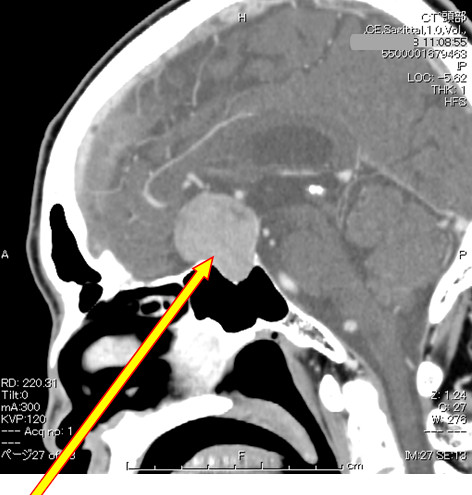

腫瘍が大きくなって下垂体の上にある視交叉(視神経)を圧迫すると視力、視野障害が出現します。視野は両側の外側が見えにくくなる(両耳側半盲)場合が多いです。頭痛もよく見られます。下垂体腺腫を持っている人に突然のひどい頭痛が生じたときには下垂体卒中といって腫瘍の中で出血や梗塞を起こしていることがありますので、すぐに脳神経外科を受診する必要があります。また正常な下垂体組織が障害を受けて下垂体機能低下症(別項参照リンク)をきたすことがあり、1cm以上の非機能性下垂体腺腫の58%の患者さんになんらかのホルモン分泌低下があったという報告があります。

下垂体腺腫に対する手術治療の第一選択は、経鼻的摘出となっており、内視鏡の発達により、従来は開頭手術を要した比較的大きな下垂体腺腫も、内視鏡下に経鼻摘出されます。